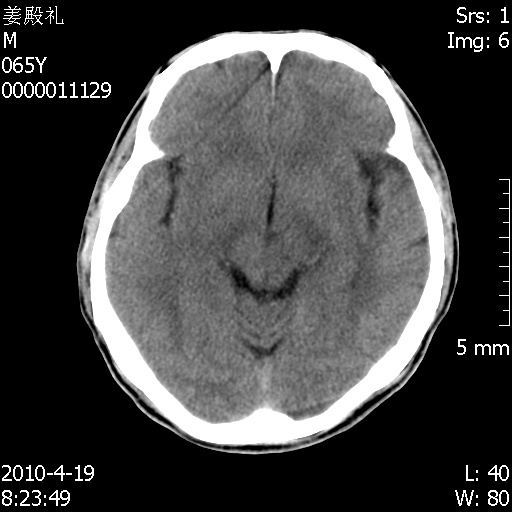

老年男性,突发左下肢无力1天,其余有价值的检查都没有。平扫ct值大约60hu,增强后ct值没什么改变,请大家讨论一下这个病例是什么?说明诊断理由。

左小脑、右大脑顶叶多发圆形高密度病灶,其周环状低密度影。考虑多发脑出血。隔期观察。

今天上班后发现病人前天复查(4月18日发病,19日初诊,22日复查),三个病灶均明显增大,边缘仍旧清楚,水肿加重,右侧脑室基本闭塞。

我想:如果是肿瘤出血的话,一般不会导致体积明显改变,水肿又进一步加重;如果是出血灶,那么现在应该正好是水肿加重的时候,还是比较符合,但是为什么边缘又是这样的特点?

遗憾! 复习了复查片:发现顶叶出血灶破入侧脑室,侧脑室体部见少许高密度。